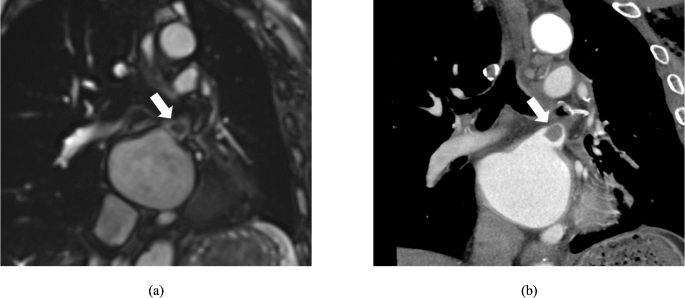

Representative cases are shown in Fig. 2.

A 76-year-old man with lung cancer who underwent left upper lobectomy. Postoperative cine-MRI (a) and contrast-enhanced cardiac CT (b) show thrombus in the left superior pulmonary vein stump (arrows). Volumetric analysis of the cine-MR images reveals a large left atrial end-systolic volume (102.7 mL) (LAESVI, 62.5 mL/m2), large left atrial end-diastolic volume (75.8 mL) (LAEDVI, 46.1 mL/m2), and low ejection fraction (26.2%). LAESVI = left atrial end-systolic volume index; LAEDVI = left atrial end-diastolic volume index.